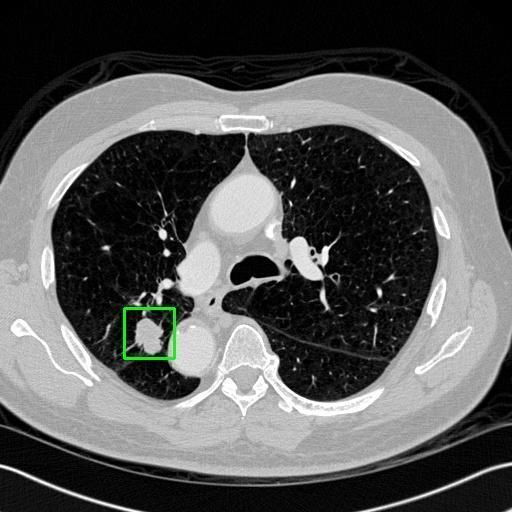

We developed an AI-based system using deep learning models for analyzing lung CT scans to detect and classify pulmonary nodules. We chose the YOLOv11 architecture for its enhanced object detection capability and adapted it specifically for medical imaging, incorporating pixel-level precision and severity classification.

Classification into three severity levels with colored bounding boxes.

Successfully built and deployed an AI model (YOLOv11) capable of detecting lung nodules in CT scans with high accuracy and real-time performance.

Designed a severity classification system that categorizes nodules into null, moderate, and severe using colored bounding boxes, assisting in rapid clinical decision-making.